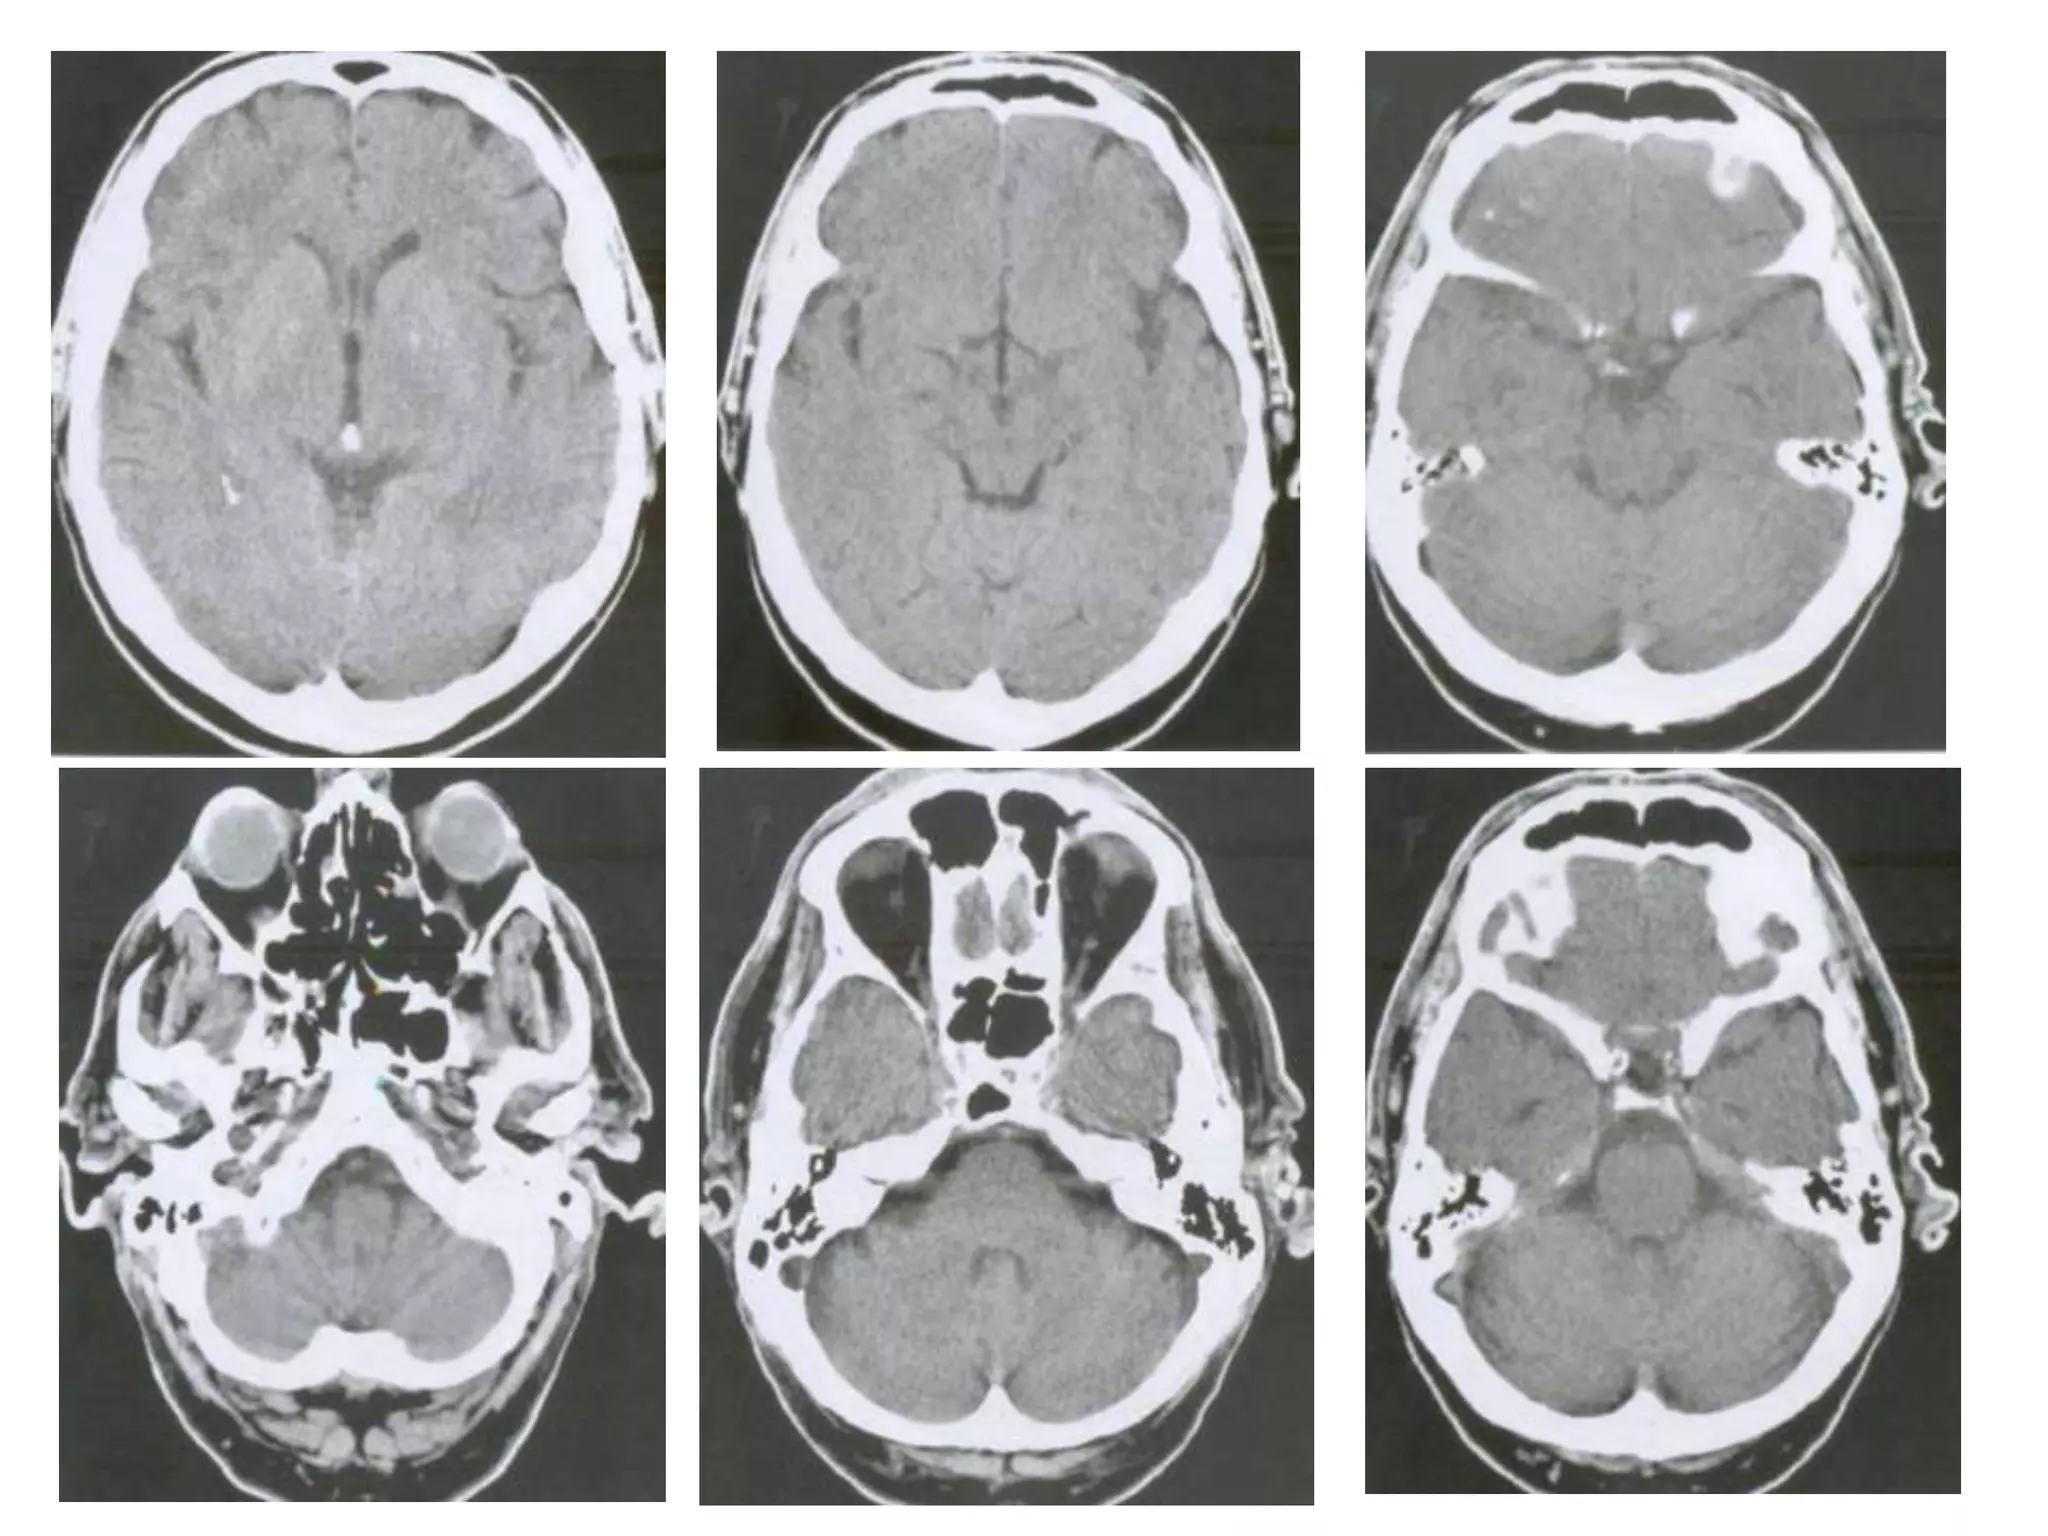

• On axial CT , structures medial to line of tentorial

edge are infratentorial and those lateral are

supratentorial.

VENTRICULAR SYSTEM

   Lateral ventricles – Telencephalon ( cerebral hemisheres)

   3rd ventricle      – Diencehalon

   Sylvian aqueduct – Mesencephalon (midbrain)

   4th ventricle      – hind brain (pons+medulla)

• Saggital and Coronal T1 weighted MRI – accurate

assessment of ventricles and C. callosum

• Mid Saggital section – for shape and configuration

of Aqueduct of Sylvius.

Radiology

• Axial MRI / CT – ‘kidney bean’ turned on its side.

• Saggital MRI - mid point of line drawn b/w T. sella

and trocula should intersect middle of 4th

ventricle.

• Coronal MRI – elongated rhomboid shape